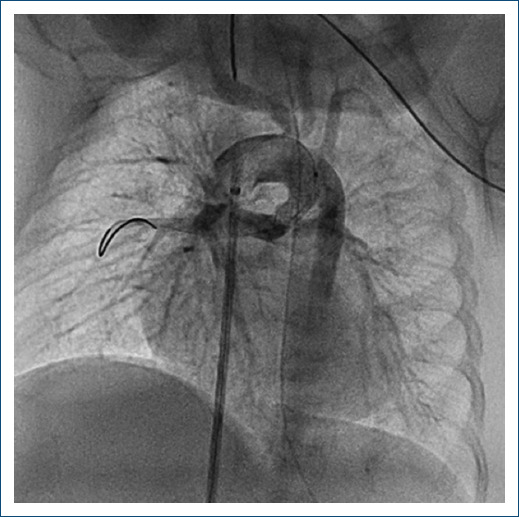

Abstract Image